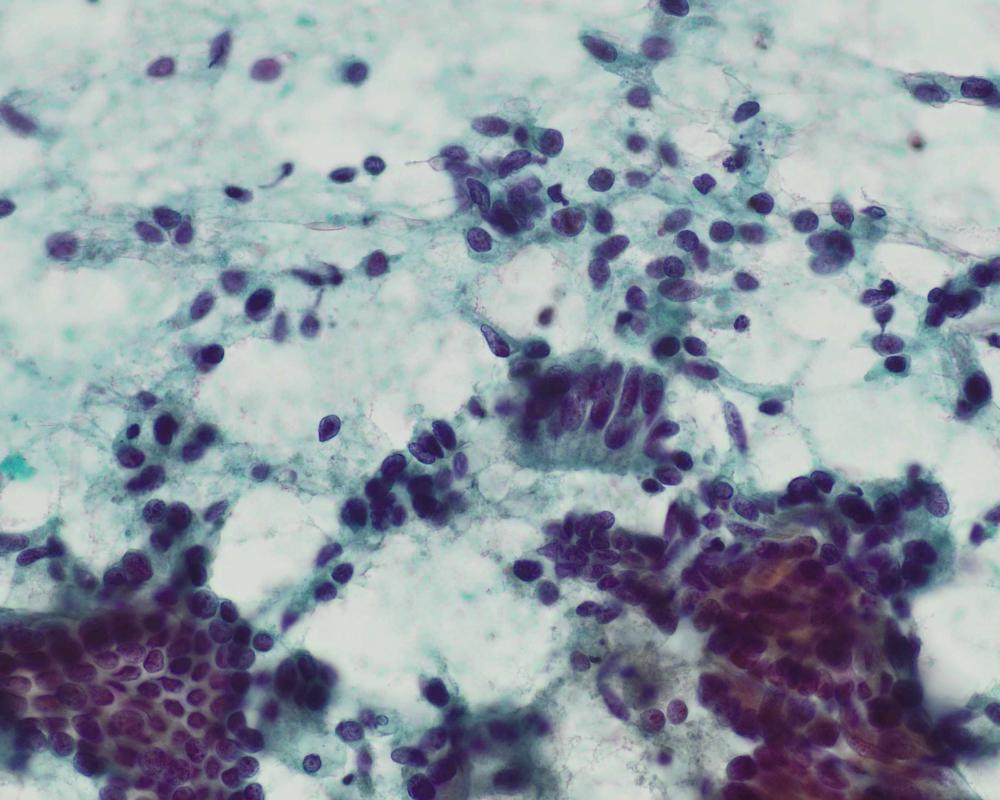

種別:呼吸器

出題:○古賀 裕1、山本 将義2、藤本 翔大2.1国立病院機構 九州がんセンター 病理診断科、2国立病院機構 九州がんセンター 臨床検査科

| 年齢 | 60歳代 | 性別 | 男性 |

| 採取部位 | 肺腫瘍 | 採取方法 | 捺印 |

既往歴:59歳 前立腺癌に対してホルモン治療、放射線治療、59歳高血圧、63歳糖尿病で内服加療中

現病歴:前立腺癌の経過観察のCTにて右肺結節を指摘された。PSA含めて腫瘍マーカーは正常であった。本標本は術中迅速組織診断用に提出された肺腫瘍の捺印細胞診検体である。

| 正解 | 5.転移性肺腫瘍(前立腺癌) |

| 1.類基底細胞型扁平上皮癌 | 9件 | (11.2%) | |

| 2.大細胞神経内分泌癌 | 5件 | (6.2%) | |

| 3.腸型腺癌 | 42件 | (52.5%) | |

| 4.転移性肺腫瘍(大腸癌) | 14件 | (17.5%) | |

| 5.転移性肺腫瘍(前立腺癌) | 10件 | (12.5%) | |

| 投票総数 | 80件 | (100%) |